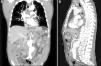

Abdominal aortic aneurysm is a relatively common condition associated with well-defined cardiovascular risk factors. A 74-year-old Caucasian man with a 100-pack-year history of cigarette smoking and generalized atherosclerotic disease manifested by symptomatic carotid artery disease and peripheral artery disease presented to our department for assessment of severe abdominal pain. Physical examination was unremarkable, except for a tender and pulsatile periumbilical mass. A contrast-enhanced computed tomography scan showed an aortic aneurysm with circumferential mural thrombosis extending from below the renal arteries to the bifurcation of the common iliac arteries, without evidence of rupture or dissection (Figure 1A and B). Three-dimensional angiographic reconstruction revealed a complex bilobular aneurysm, the proximal and distal segments measuring 6.6 cm×5.6 cm and 7.5 cm×6.8 cm, respectively, in transverse diameters (Figure 2A and B; Supplementary Data, Videos 1 and 2). The patient underwent elective surgery three months later, with successful aorto-aortic graft insertion.

This case illustrates the usefulness of three-dimensional computed tomography angiography in the assessment of the location and anatomy of aortic aneurysms, providing a valuable non-invasive tool for selecting the appropriate surgical procedure. The rare morphology of this aneurysm, in particular, resembles that of a human fetus in the uterus, giving it an unusual and curious radiological appearance.